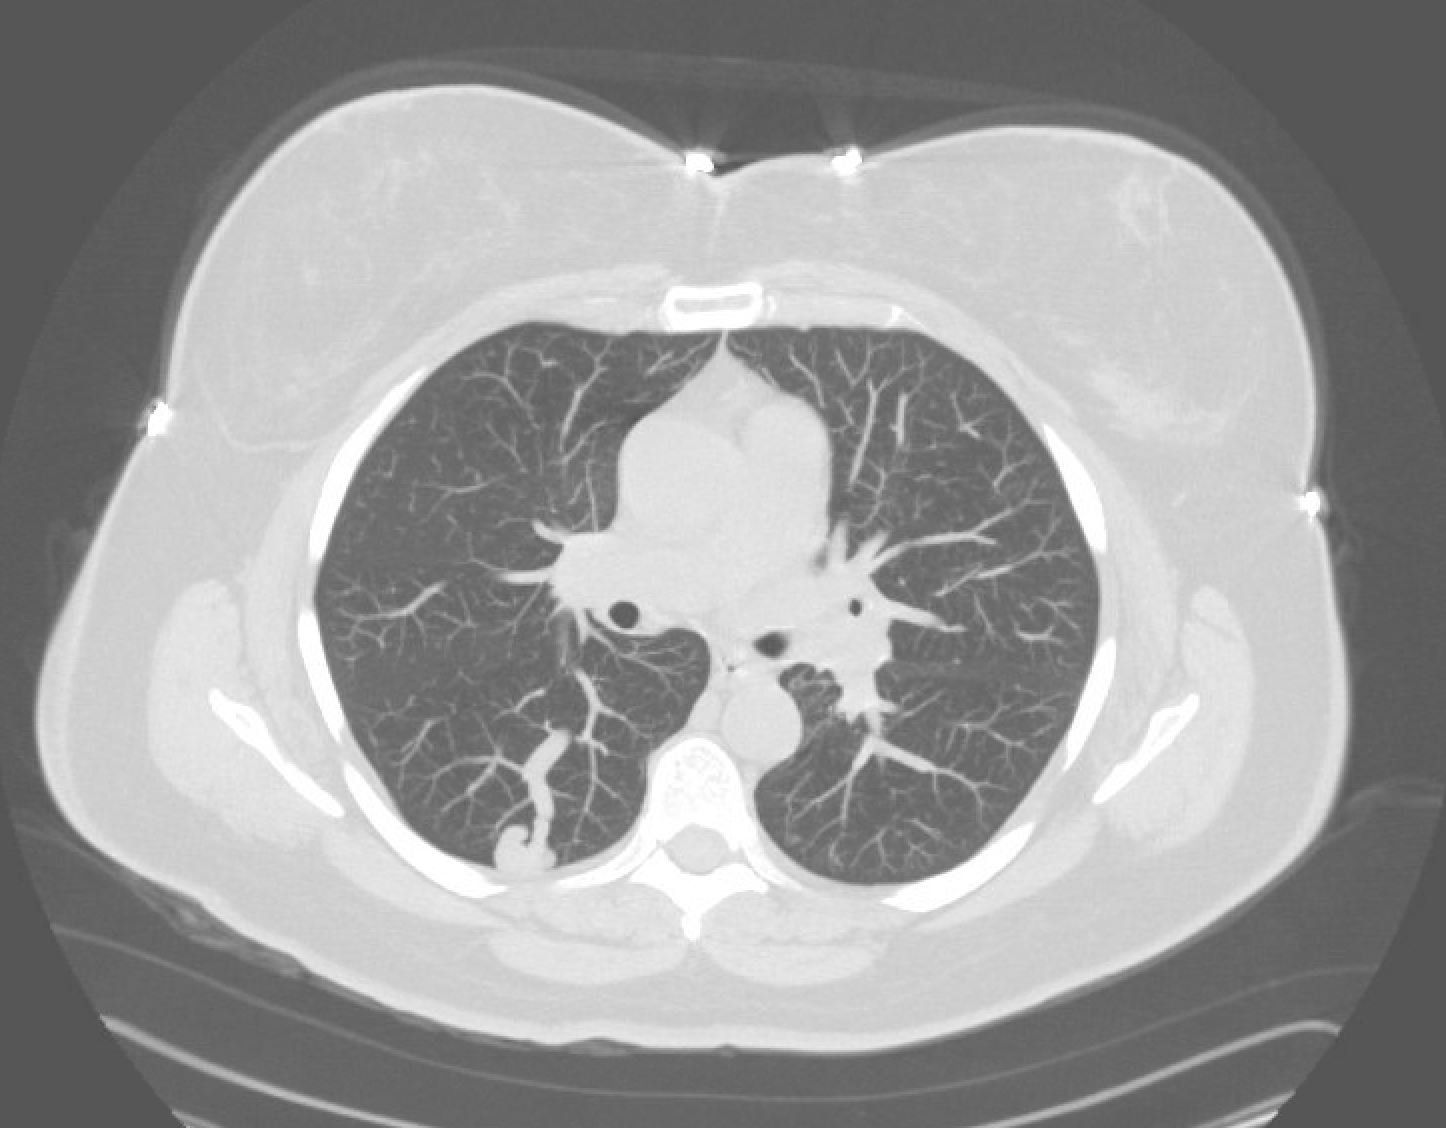

CT chest demonstrating a pulmonary AVM — feeding segmental pulmonary artery, aneurysmal sac, and draining vein to the left atrium.

Pre-procedure CT: map each PAVM, feeding artery diameter, number of feeders, draining vein, and proximity to normal branches.